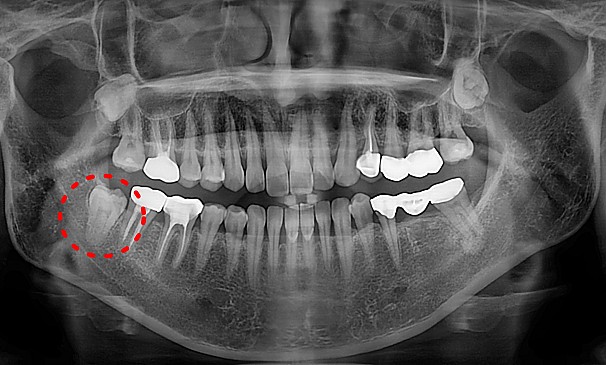

자가치아이식술란?

도저히 살릴 수 없는 치아를 뽑고 그 자리에 자신의 사랑니를 이식하는 치료방법입니다.

기능이 없는 사랑니를 이동하여 이식함으로써 내 자연치아를 사용할 수 있습니다.

모OO님 전후사진 | 치료 기간 : 2주

치료 전